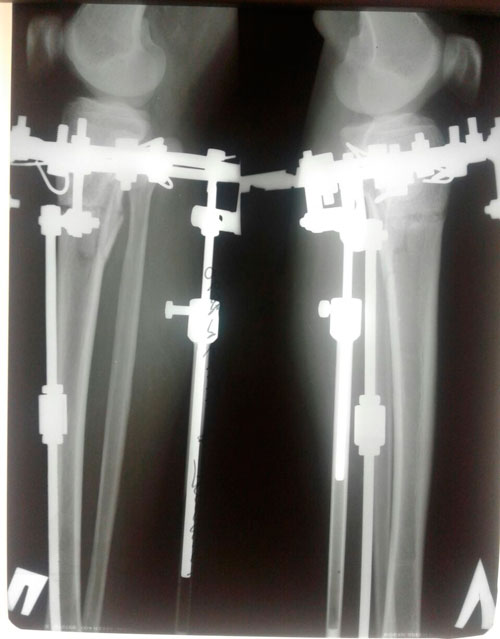

Исходник 28 лет Актобе.

Дата операции 14.02.2018г.

Дата снятия аппаратов 12.06.2018г.

Срок лечения 120 дней.